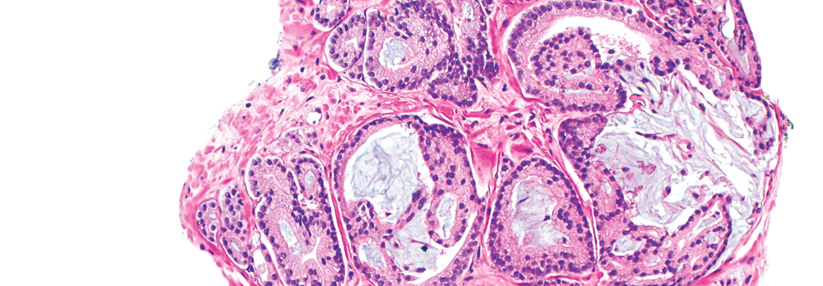

Die Zugabe von Apalutamid zu einer Androgendeprivation brachte Patienten mit metastasiertem hormonsensitivem Prostatakarzinom in der TITAN-Studie einen signifikanten Überlebensvorteil. Die finale Analyse bestätigt nun die initialen Ergebnisse: Mit der Kombination war das Sterberisiko, verglichen mit einer alleinigen Androgendeprivation, um fast die Hälfte verringert.

Der AR*-Inhibitor Apalutamid ist zur Behandlung von Patienten mit metastasiertem hormonsensitivem Prostatakarzinom (mHSPC­) in Kombination mit einer Androgendeprivationstherapie (ADT) zugelassen. Grundlage bildeten die Ergebnisse der Phase-3-Studie TITAN. Darin hatten kanadische Forscher um Professor Dr. Kim N. Chi, BC Cancer and Vancouver Prostate Centre, 1052 erkrankte Männer eingeschlossen. Sie randomisierten die Teilnehmer 1:1 zu einer ADT plus Apalutamid oder einer Scheintherapie.

Bereits in der Interimsanalyse erreichte die Studie ihre primären Endpunkte: Mit der Addition des AR-Hemmers verlängerte sich das Überleben ohne radiographischen Progress (Hazard Ratio [HR] 0,48; p < 0,001)…